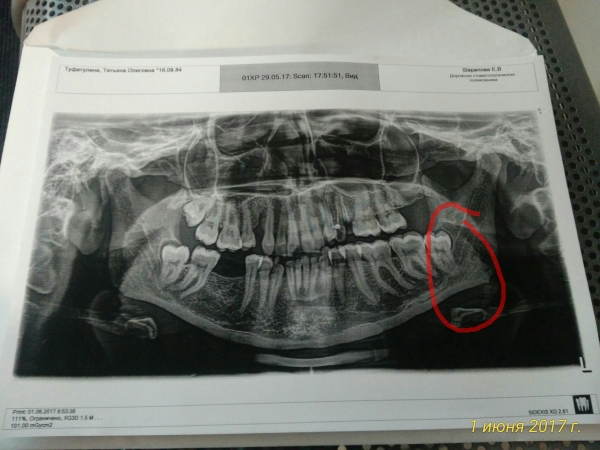

29 мая мне срезали капюшон у зуба мудрости. После наркоза было больно глотать и открывать рот, но он открывался.

На сегодняшний день глотать стало легче, но рот все равно открывать дискомфортно. Врач настаивает на удалении зуба. Но нерв проходит очень близко.

На снимке, представленном Вами видно, что зубу мало места в зубном ряду. Поэтому он будет сдвигать остальные зубы, а также вызывать болевые ощущения.

Открывание рта со временем восстановится. После удаления, возможно, будет онемение со стороны причинного зуба до подбородка.